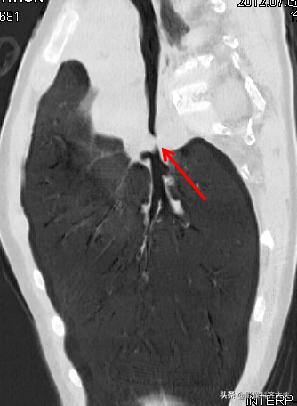

CT冠状位重建明确显示左侧自气管阻塞,有明确异物的存在,红色箭头所示。